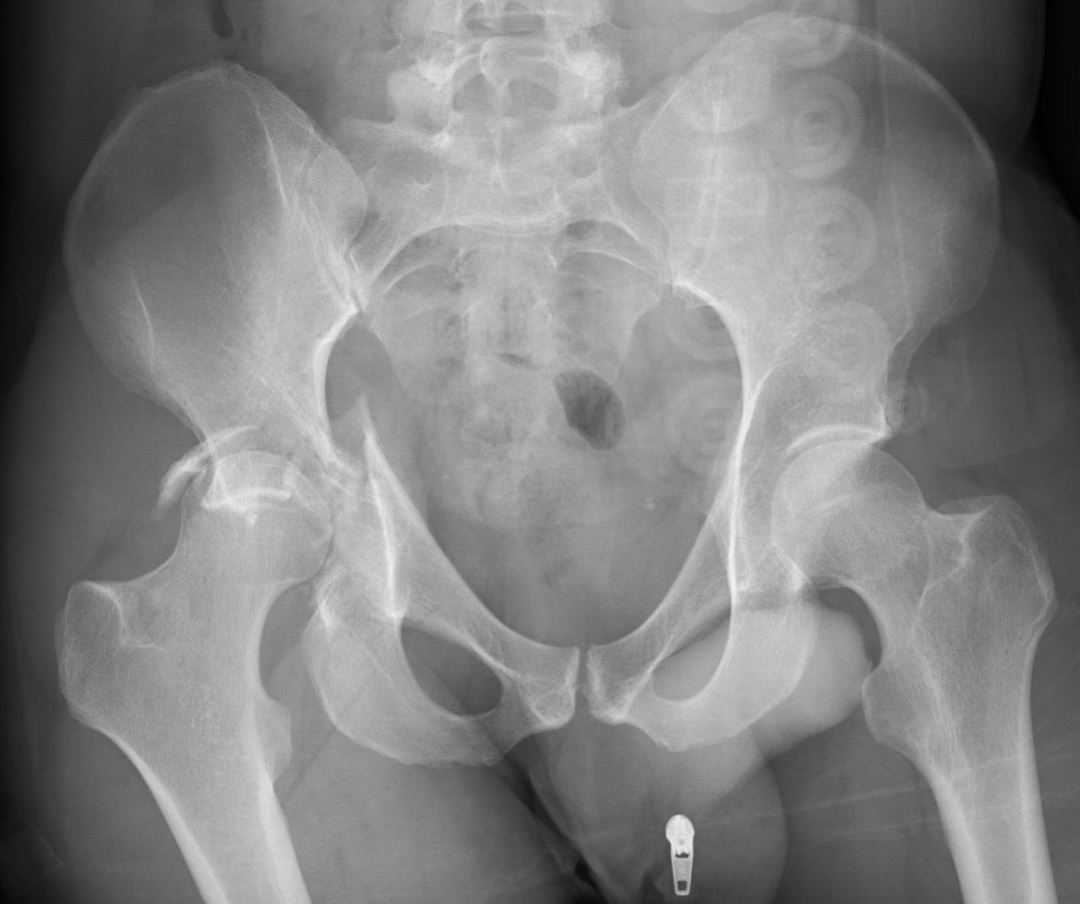

Het bekken

Het bekken vormt een verbinding tussen de wervelkolom en de benen. Het bekken bestaat uit meerdere botten: een linker en een rechter heupbeen en het heiligbeen aan de achterkant. Eén heupbeen is weer opgebouwd uit verschillende onderdelen: een darmbeen, een zitbeen en een schaambeen. Op de overgang van deze drie onderdelen van het heupbeen bevindt zich aan beide kanten een heupkom (het zogenaamde ‘acetabulum’). Van bovenaf gezien heeft het bekken een vorm van een soort ring: het heiligbeen aan de achterkant, de darmbeenderen aan de zijkanten en het schaam- en zitbeenderen aan de voorkant. Aan de achterkant zijn de darmbeenderen met sterke banden aan het heiligbeen verbonden, aan de voorkant zijn beide schaambenen in het midden met elkaar verbonden met sterke banden. Bij vrouwen is het bekken breder en is de ring ruimer dan bij mannen, dit om de geboorte van een kind mogelijk te maken.

Het bekken kan op veel verschillende plaatsen breken. Bovendien kan het op meerdere plaatsen tegelijk breken. Afhankelijk van de plaats van de breuk en het aantal breuken is hiervoor veel energie of relatief weinig energie voor nodig. Zo kan bij een simpele val het zitbeen of het heiligbeen al vrij eenvoudig breken, zeker als met de leeftijd het bot brozer wordt (osteoporose). Voor het breken van het bekken ter hoogte van de heupkom of aan de achterkant bij het heiligbeen, is vaak meer energie nodig. Zeker bij jongeren ontstaat dit vaak pas bij een verkeersongeval of een val van hoogte.

Een traumachirurg maakt onderscheid of het bekken alleen aan de voorkant (ter hoogte van het zit- of schaambeen) kapot is, of ook aan de achterkant gebroken is (ter hoogte van het heiligbeen). Naast gewone Rontgenfoto’s is het soms nodig hiervoor een aanvullende CT scan te maken. Indien de ring van het bekken aan zowel de voorkant als aan de achterkant gebroken is, dan is er mogelijk sprake van een instabiel bekken en kan het nodig zijn een stabiliserende operatie te verrichten. Deze instabiliteit van de ring kan ook ontstaan indien er een combinatie is van een breuk aan de voorkant en een letsel van de banden aan de achterkant. Ook in dat geval is de bekkenring instabiel en is er een kans dat het bekken met behulp van een operatie gestabiliseerd moet worden. In enkele gevallen kunnen de banden aan de voorkant en achterkant gescheurd zijn zonder dat er sprake is van een breuk, maar toch is er dan sprake van een ernstig instabiel bekken. Dit moet dan eigenlijk altijd geopereerd worden.